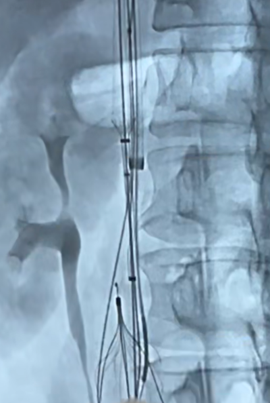

Through and through wire was achieved from popliteal to IJV and the 14fr IJV sheath was advanced past the IVCF struts to act as a protection for the basket and coring element of the ClotTriever for thrombectomy of the IVC and iliofemoral veins as several passes were made. There was satisfactory clearance of clots from the left iliofemoral veins. Aspiration of the IVCF was then performed with a FlowTriever 16 catheter but there was incomplete thrombectomy with some of the remnant clots being pushed above the IVC filter. The IJV sheath was upsized to 16F over and the sheath was used to protect the ClotTriever as it passed though the filter. The through and through Rosen wire (Cook Medical, Bloomington, Indiana) was subsequently pulled back from the IJV and cannulated into the right subclavian vein. The ClotTriever was then deployed next to the 16Fr sheath above the filter as an embolic protection device. The thrombosed IVC filter was then retrieved with a Clover snare (Cook Medical, Bloomington, Indiana). From the IJV sheath, FlowTriever disks were deployed and further thrombectomy of the remnant IVC thrombus was performed which yielded even more thrombus.

Completion venogram showed brisk return of flow and patency.